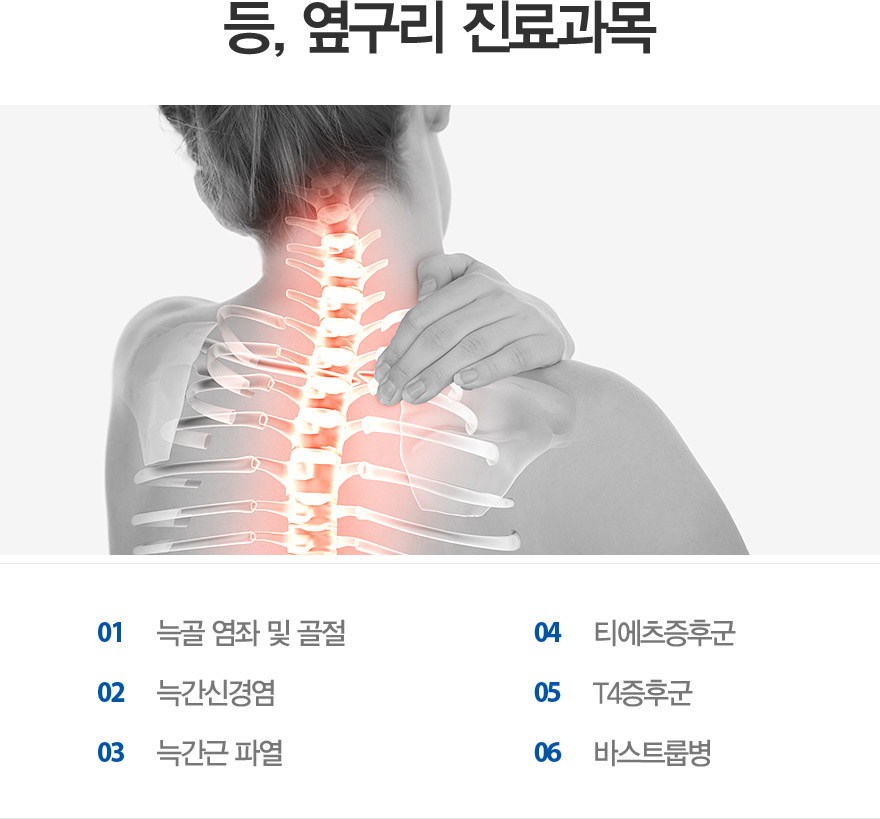

3. Ею, ПЗБИИЎ

ДСАё ПАСТ Йз АёР§, ДСАЃНХАцПА, ДСАЃБй ЦФП, ЦМПЁУїСѕШФБК, T4СѕШФБК, ЙйНКЦЎЗьКД

3. Ею, ПЗБИИЎ

ДСАё ПАСТ Йз АёР§, ДСАЃНХАцПА, ДСАЃБй ЦФП, ЦМПЁУїСѕШФБК, T4СѕШФБК, ЙйНКЦЎЗьКД

3. Ею, ПЗБИИЎ

ДСАё ПАСТ Йз АёР§, ДСАЃНХАцПА, ДСАЃБй ЦФП, ЦМПЁУїСѕШФБК, T4СѕШФБК, ЙйНКЦЎЗьКД

3. Ею, ПЗБИИЎ

ДСАё ПАСТ Йз АёР§, ДСАЃНХАцПА, ДСАЃБй ЦФП, ЦМПЁУїСѕШФБК, T4СѕШФБК, ЙйНКЦЎЗьКД